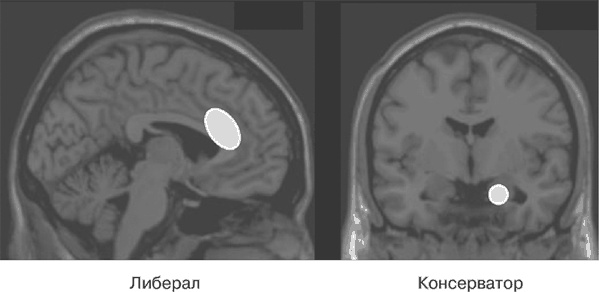

Ученые обнаружили много интересного в обеих областях мозга (рисунок 29). Сингулярная кора, расположенная в передней части мозга между двумя полушариями, будет в большей степени развита у представителей либерального лагеря. А зона правой миндалины будет больше развита у тех, кто придерживается консервативных взглядов, причем ее развитие напрямую зависит от стойкости и выраженности консервативных убеждений.

Иллюстрация к книге — Почему девочки не хуже мальчиков разбираются в математике [i_029.jpg]

Рис. 29. Если вы придерживаетесь либеральных взглядов, у вас будет в большей степени развита сингулярная кора, а зона миндалины будет более развита в том случае, если вы по убеждениям консерватор

Как бы там ни было, но выявить непосредственную связь между этими двумя фактами не удалось. Хотя общий вывод таков: эти зоны не являются центрами, определяющими, за кого – за правых или за левых – вы будете голосовать на выборах, но степень их развития, судя по всему, связана с чертами характера, влияющими на политическую ориентацию.

Нет, это науке пока не известно. И именно в этом заключается одна из многих проблем, на решение которых нацелено это исследование. Можно было бы наивно предположить, что видные специалисты, работающие в области исследования мозга, рано или поздно определят точную функцию каждой его зоны. Но скажу честно: нет большего заблуждения, чем это. Что же касается упомянутых нами областей, то есть сингулярной коры и миндалины, то они обеспечивают реализацию бесчисленных ментальных функций. Авторы исследования выбрали из тысячи возможных интерпретаций ту, которая наиболее убедительно подтверждает их гипотезу. Они предполагают, что поголовно все консерваторы являются боязливыми людьми, с необоснованной тревогой реагирующими на обстоятельства, несущие потенциальную угрозу. И нам действительно известно, что миндалина активизируется в том случае, если вы видите что-то, что внушает вам страх. И наоборот, они считают, что либералы в большей степени обладают способностью противостоять конфликтным ситуациям, исход которых непредсказуем, осуществляя выбор в пользу именно таких ситуаций. И нам также известно, что сингулярная кора активизируется в тех случаях, когда нам предстоит сделать выбор среди нескольких возможных вариантов для разрешения того или иного конфликта («Должен ли я сделать то или это?»). Тем не менее я хотел бы повторить еще раз, что это всего лишь одна из множества возможных интерпретаций и что ничто в исследовании, о котором я вам только что говорил, не может являться ее абсолютным подтверждением.